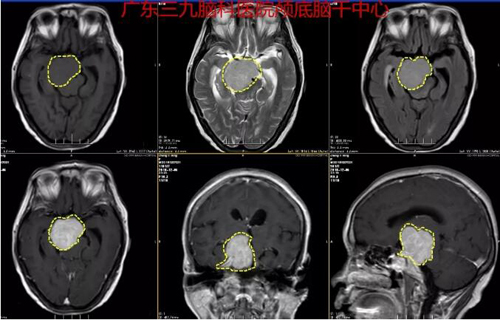

图2:术前MR示右侧岩斜区示一分叶状占位性病变,范围约4.4*4.7*4.7cm,病灶侵及鞍内及右侧海绵窦,包绕右侧劲内动脉。